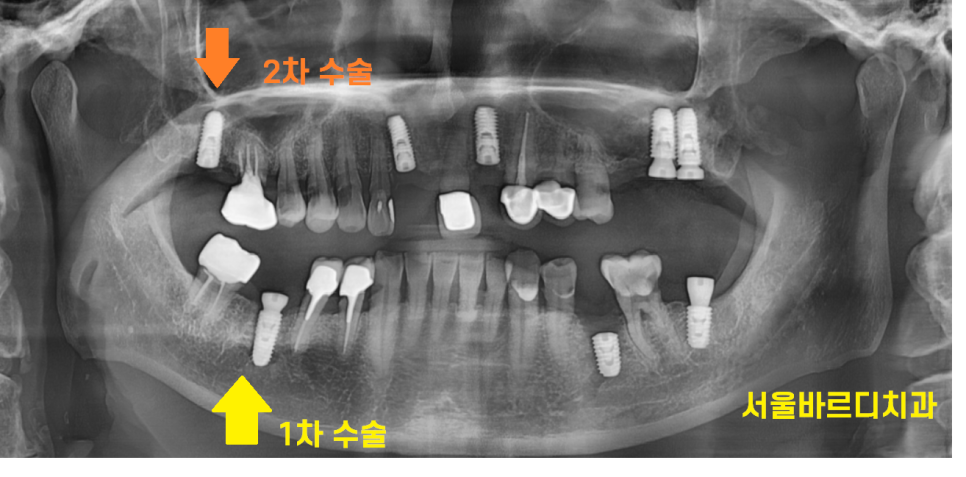

먼저 x-ray 한장을 보실께요~

240223

위의 사진을 보시면 아시겠지만

뚜껑이 있는게 있고

없는게 있죠~?

뚜껑이 있는 것은 1차 수술법으로 치료

뚜껑이 없는 것이 임플란트 2차 수술이 필요한 것들입니다.

231109

또한 임플란트 치료가 끝날 때까지

임시 틀니를 쓰셔야하는 전악 임플란트 환자분

앞니 임플란트 수술 환자분들은 2차 수술법으로 진행합니다.